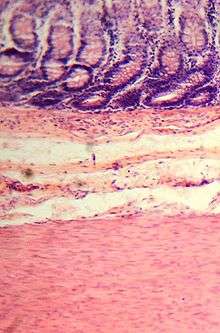

Histology

Colonic crypts

The wall of the large intestine is lined with simple columnar epithelium with invaginations. The invaginations are called the intestinal glands or colonic crypts.

The colon crypts are shaped like microscopic thick walled test tubes with a central hole down the length of the tube (the crypt lumen). Four tissue sections are shown here, two cut across the long axes of the crypts and two cut parallel to the long axes. In these images the cells have been stained by immunohistochemistry to show a brown-orange color if the cells produce a mitochondrial protein called cytochrome c oxidase subunit I (CCOI). The nuclei of the cells (located at the outer edges of the cells lining the walls of the crypts) are stained blue-gray with haematoxylin. As seen in panels C and D, crypts are about 75 to about 110 cells long. Baker et al.[24] found that the average crypt circumference is 23 cells. Thus, by the images shown here, there are an average of about 1,725 to 2530 cells per colonic crypt. Nooteboom et al.[25] measuring the number of cells in a small number of crypts reported a range of 1500 to 4900 cells per colonic crypt. Cells are produced at the crypt base and migrate upward along the crypt axis before being shed into the colonic lumen days later.[24] There are 5 to 6 stem cells at the bases of the crypts.[24]

As estimated from the image in panel A, there are about 100 colonic crypts per square millimeter of the colonic epithelium.[11] Since the average length of the human colon is 160.5 cm[10] and the average inner circumference of the colon is 6.2 cm.[11] the inner surface epithelial area of the human colon has an average area of about 995 sq cm, which includes 9,950,000 (close to 10 million) crypts.

In the four tissue sections shown here, many of the intestinal glands have cells with a mitochondrial DNA mutation in the CCOI gene and appear mostly white, with their main color being the blue-gray staining of the nuclei. As seen in panel B, a portion of the stem cells of three crypts appear to have a mutation in CCOI, so that 40% to 50% of the cells arising from those stem cells form a white segment in the cross cut area.

Overall, the percent of crypts deficient for CCOI is less than 1% before age 40, but then increases linearly with age.[23] Colonic crypts deficient for CCOI in women reaches, on average, 18% in women and 23% in men by 80–84 years of age.[23]

Crypts of the colon can reproduce by fission, as seen in panel C, where a crypt is fissioning to form two crypts, and in panel B where at least one crypt appears to be fissioning. Most crypts deficient in CCOI are in clusters of crypts (clones of crypts) with two or more CCOI-deficient crypts adjacent to each other (see panel D).[23]